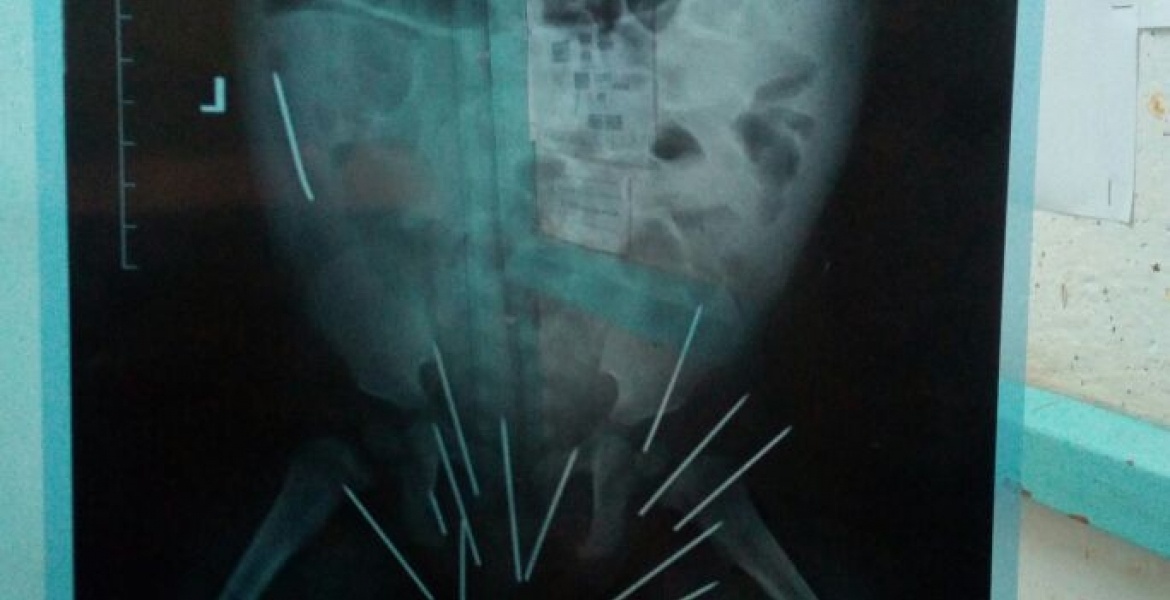

Người mẹ khẳng định không đâm kim vào mông con và không hiểu vì sao chúng lại nằm trong cơ thể bé.